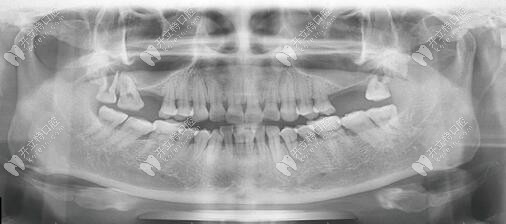

重度牙周病人的種植牙歷程:上頜六顆下頜四個(gè)牙樁

如果全口重度牙周炎不治療會(huì)發(fā)生什么變化?一般就會(huì)在5-6內(nèi)牙齒全部掉過,不信的話就來看看重度牙周病人的種植牙歷程。